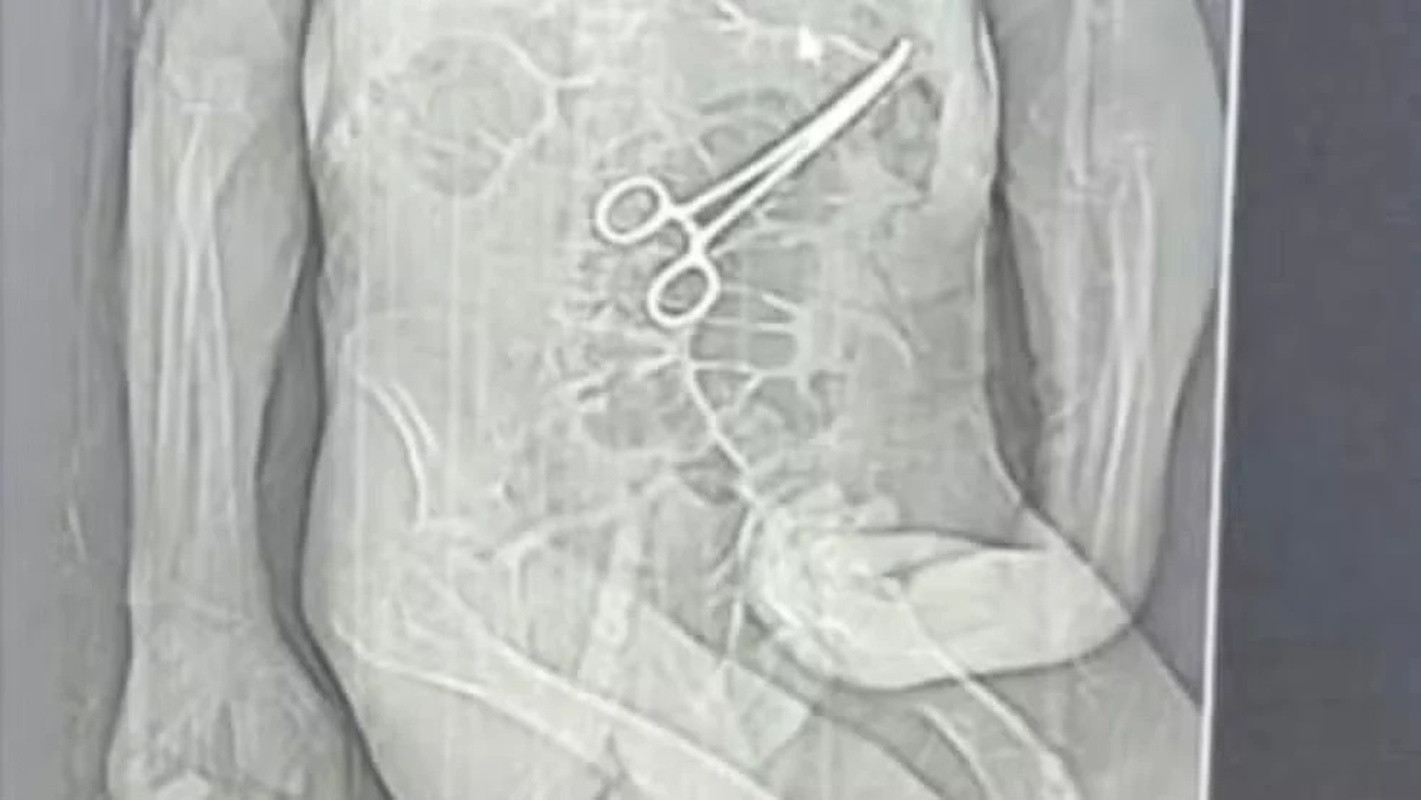

A segurança do paciente é um pilar fundamental da medicina moderna. No entanto, um recente e trágico caso vem a público para nos lembrar, de forma contundente, das consequências devastadoras de um simples deslize. A Secretaria de Saúde de um município brasileiro confirmou um grave erro cirúrgico: a equipe deixou uma pinça cirúrgica no abdômen do paciente Manoel Cardoso após um procedimento. Este corpo estranho, portanto, desencadeou uma série de complicações que, infelizmente, culminaram no óbito do homem após uma segunda cirurgia de emergência.

No caso do Sr. Manoel Cardoso, a própria Secretaria de Saúde admitiu a falha. Após o paciente apresentar fortes dores e complicações pós-operatórias, exames de imagem identificaram o objeto metálico em seu abdômen. Imediatamente, a equipe médica realizou uma nova intervenção para tentar remover a pinça. No entanto, o dano já estava feito. O corpo estranho provavelmente causou lesões internas, infecções severas ou outras intercorrências que o organismo não conseguiu suportar. Este episódio, portanto, vai além de um mero acidente; ele evidencia uma ruptura em múltiplos protocolos de segurança.